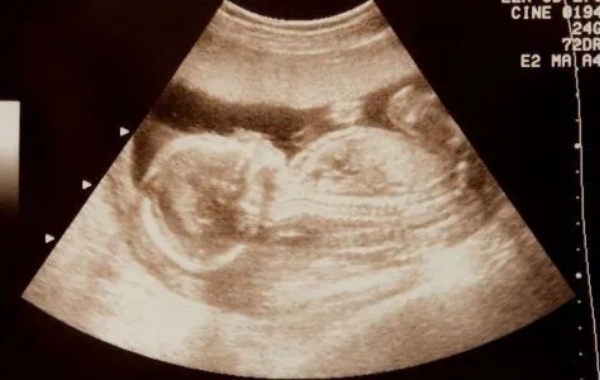

孕12周建档和nt可以当天一起做。因为建档和nt的检查项目并不冲突,而且检查结果也是一样的,nt主要是通过b超测量胎儿颈项部皮下无回声透明层最厚的部位,用于评估胎儿是否有可能患有唐氏综合征的一种方法,建卡需要检查的项目包括血压、体重等,能够判断孕妇的身体情况以及胎儿的发育情况,两者之间没有影响。孕妇在怀孕期间需要定期到医院进行产检,能够了解胎儿的生长发育情况,建档和nt都是比较重要的,通常可以当天

怀孕12周nt已过有可能还会胎停。因为nt检查没有问题只能排除明显染色体异常,不能完全排除胎停的风险,造成胎停的原因是多样的,胎停可能会发生在妊娠的每一个阶段,就算这个时候nt过了,也不能掉以轻心,还需要继续关注胎儿的生长发育情况。nt检查一般是指通过b超测量胎儿颈项部皮下无回声透明层最厚的部位,用于评估胎儿结构畸形及患有唐氏综合征的概率,虽然查nt可以评估早期妊娠中的某些风险因素,但并不能排除所

在试管婴儿期间,NT(Nuchal Translucency)检查是一项关键的产前面的筛查项目,平常在孕期11-十四周进行。这个检查主要通过超声波量测胎儿颈部透明带的厚薄程度,以评介胎儿是否是存留染色体异样的风险,特别是唐氏综合症。当NT值为1.0mm时,从数值上看属在正常情况下范畴内。大体上,NT值低于二点五毫米被当成是正常的,但这个规范并不是必须,仍旧要结合孕妇的详尽情形以及其他筛选结果来综合